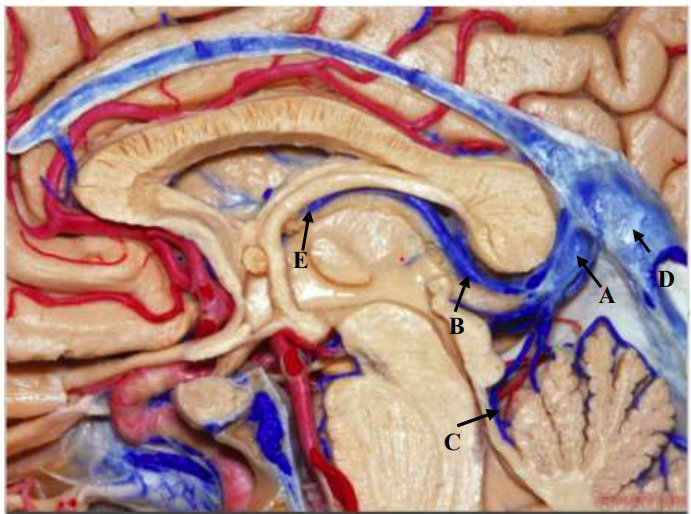

Qual seta aponta para a Veia de Galeno?

Qual seta aponta para o Nervo Facial?